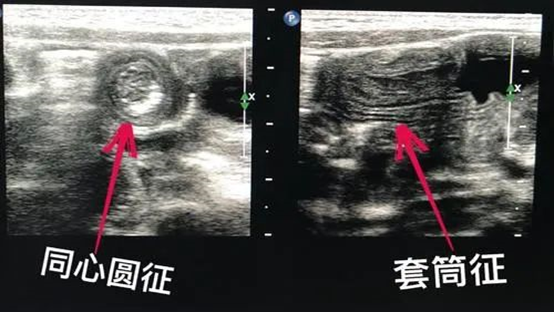

(1)、首选超声检查,其具有无创、无辐射、准确、方便、可重复等优点。但一次检查不能百分百确诊,必要时可能会反复检查或配合腹部CT诊断等。

典型肠套叠超声诊断图像